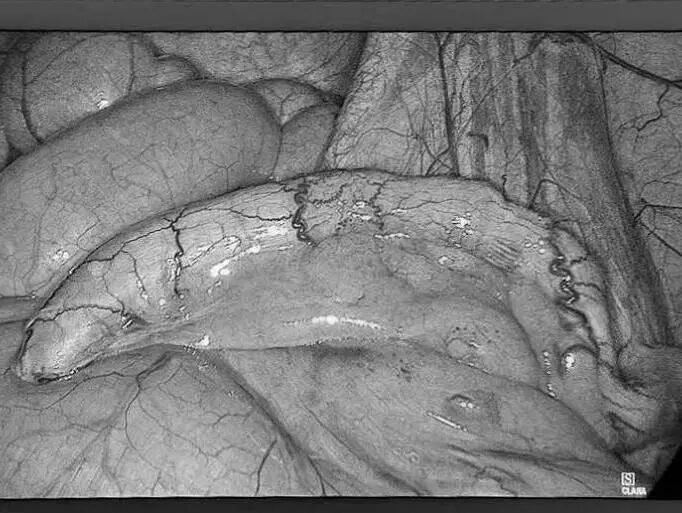

3月5日,贵州航天医院第51次晨读会由我院普外科主任、主任医师梁跃作学术交流,他以“腹腔镜下清扫No.253淋巴结的解剖问题”为题,全面讲解了No.253淋巴结的定义、清扫指征、清扫范围、相关解剖学知识等具体情况,并结合实际案例与图文对相关解剖进行了详细剖析,形象地展示了该区域复杂的解剖结构及在手术过程中可能遇到的解剖难点与要点。 普外科专家简介 梁 跃 普外科主任 主任医师 临床擅长:对普外科各类肿瘤手术具有丰富的临床经验。 毕业于遵义医学院,遵义市医学会小儿外科学分会常务委员,遵义市肛肠协会理事,遵义市医学会核医学分会(第二届)委员会委员;荣获第三期“黔医人才计划”优秀学员称号;主持市级课题1项,完成省级课题1项,在国内各类刊物上发表论文10余篇。 钱科洪 普外科 副主任医师 临床擅长:从事普外科临床工作30余年,对各类普外科疾病的诊治、乳腺、甲状腺、胃十二指肠、结直肠等疾病及疑难杂症具有丰富的临床诊疗经验。 毕业于遵义医学院临床医疗系,2009年前往中山大学附属第一医院微创外科进修学习,在国内各专业期刊发表论文数篇。 普外科简介 基本情况 贵州航天医院普外科成立于1968年,前身属于航天部O61基地3417医院外一科,3417医院、3427医院合并后更名为普外科,下设胃肠外科、肛肠外科2个亚专业科室,是中国疝病专科联盟单位,贵州医科大学附属医院胃肠外科专科联盟单位。开放床位40张,配备医护人员21人。 专科特色 普外科致力于胃肠及肛肠疾病的外科临床诊治及科研,以腹腔镜微创外科技术为本,形成以快速康复治疗胃肿瘤、结直肠肿瘤、小肠肿瘤、直肠脱垂、肥胖病、急腹症、各类疝、痔、瘘等专科特色,同时注重胃肠疾病尤其是结直肠恶性肿瘤的基础研究和临床转化研究,总体诊断和治疗水平在区域同级医院居于领先水平。 开展手术:腹腔镜下胃癌根治术,腹腔镜下袖状胃切除术,腹腔镜下胃肠道间质瘤切除术,腹腔镜下结、直肠癌根治术,胃癌、结直肠癌的精准治疗,腹腔镜下小儿疝气、成人疝修补术,腹腔镜下阑尾手术,内痔的硬化注射治疗及痔疮的微创治疗:ATH、PPH、TST,直肠脱垂的各种手术治疗,难治性伤口VSD技术,鼻胃肠管、肠梗阻导管置入术,肛肠术后间歇性导尿技术,并引进了中医适宜技术,也为各种化疗患者提供输液港安装,提高患者就医体验。 腹腔镜下腹股沟疝无张力修补术 腹腔镜下腹股沟疝 无张力修补术 腹股沟疝里金斯坦 (Lichtenstein)手术 PPH微创术治疗环状混合痔 黏连性或炎性肠梗阻-肠梗阻导管 腹腔镜袖状胃切除 腹腔镜阑尾切除术 腹腔镜阑尾肿瘤切除术 腹腔镜下结肠癌根治术 诊疗范围 胃肿瘤、结直肠肿瘤、小肠肿瘤、肥胖症、各类急腹症、腹部外伤、腹壁疝、便秘、直肠脱垂、痔疮、肛瘘、肛裂等胃肠、肛肠外科疾病。 end